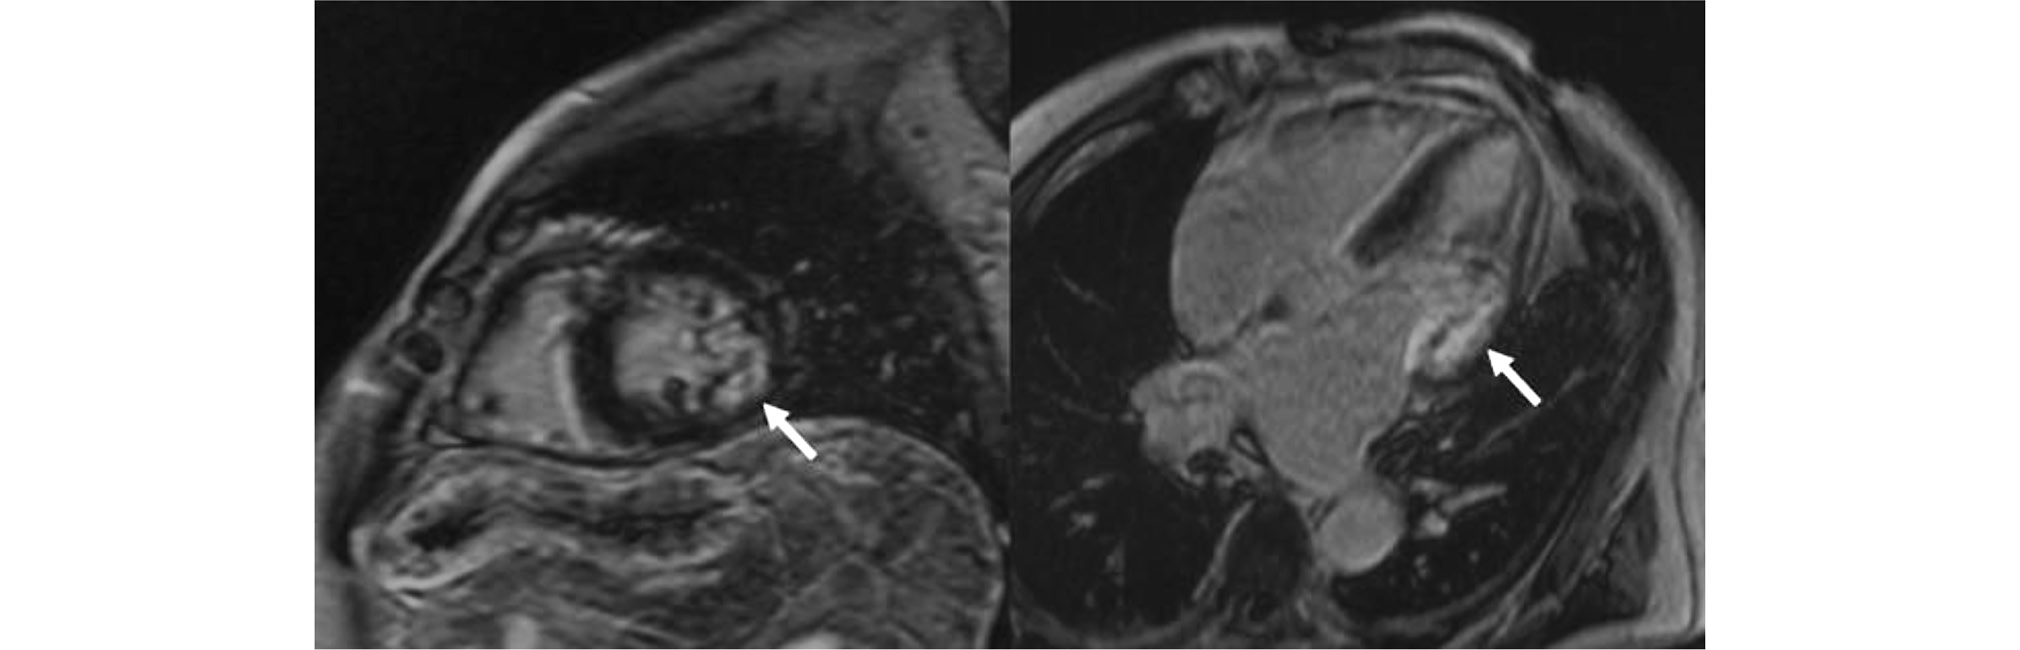

LGE was detected in all patients in Group 2 and 11 (85%) patients in Group 1 (Table 2). RV LGE was detected in all patients in Group 2 and 58% of patients in Group 1 (p < 0.05). Group 2 had a significantly higher rate of contrast uptake in the interventricular septum and RV inferior wall (62% vs. 8%, p < 0.05) (Fig. 2). A simultaneous subendocardial LGE in the LV and RV in the interventricular septum was found Group 2, resulting in the double-line sign (100% vs. 50%, p < 0.01) (Fig. 3). Atrial LGE was observed in 69% and 50% of patients in Groups 2 and 1, respectively (p > 0.05).

Fig. 3. Time-delayed contrast-enhanced cardiac magnetic resonance imaging scans in transthyretin amyloidosis. Subendocardial contrast uptake in the interventricular septum (right and left ventricular involvement) (red dashed lines).

The double-line sign in the interventricular septum in ATTR amyloidosis is an interesting phenomenon, indicating simultaneous subendocardial LGE in the LV and RV (See Fig. 3). This sign was observed in all patients with ATTR amyloidosis, possibly making it an important diagnostic marker. However, available publications do not describe this contrast uptake pattern, necessitating further studies.